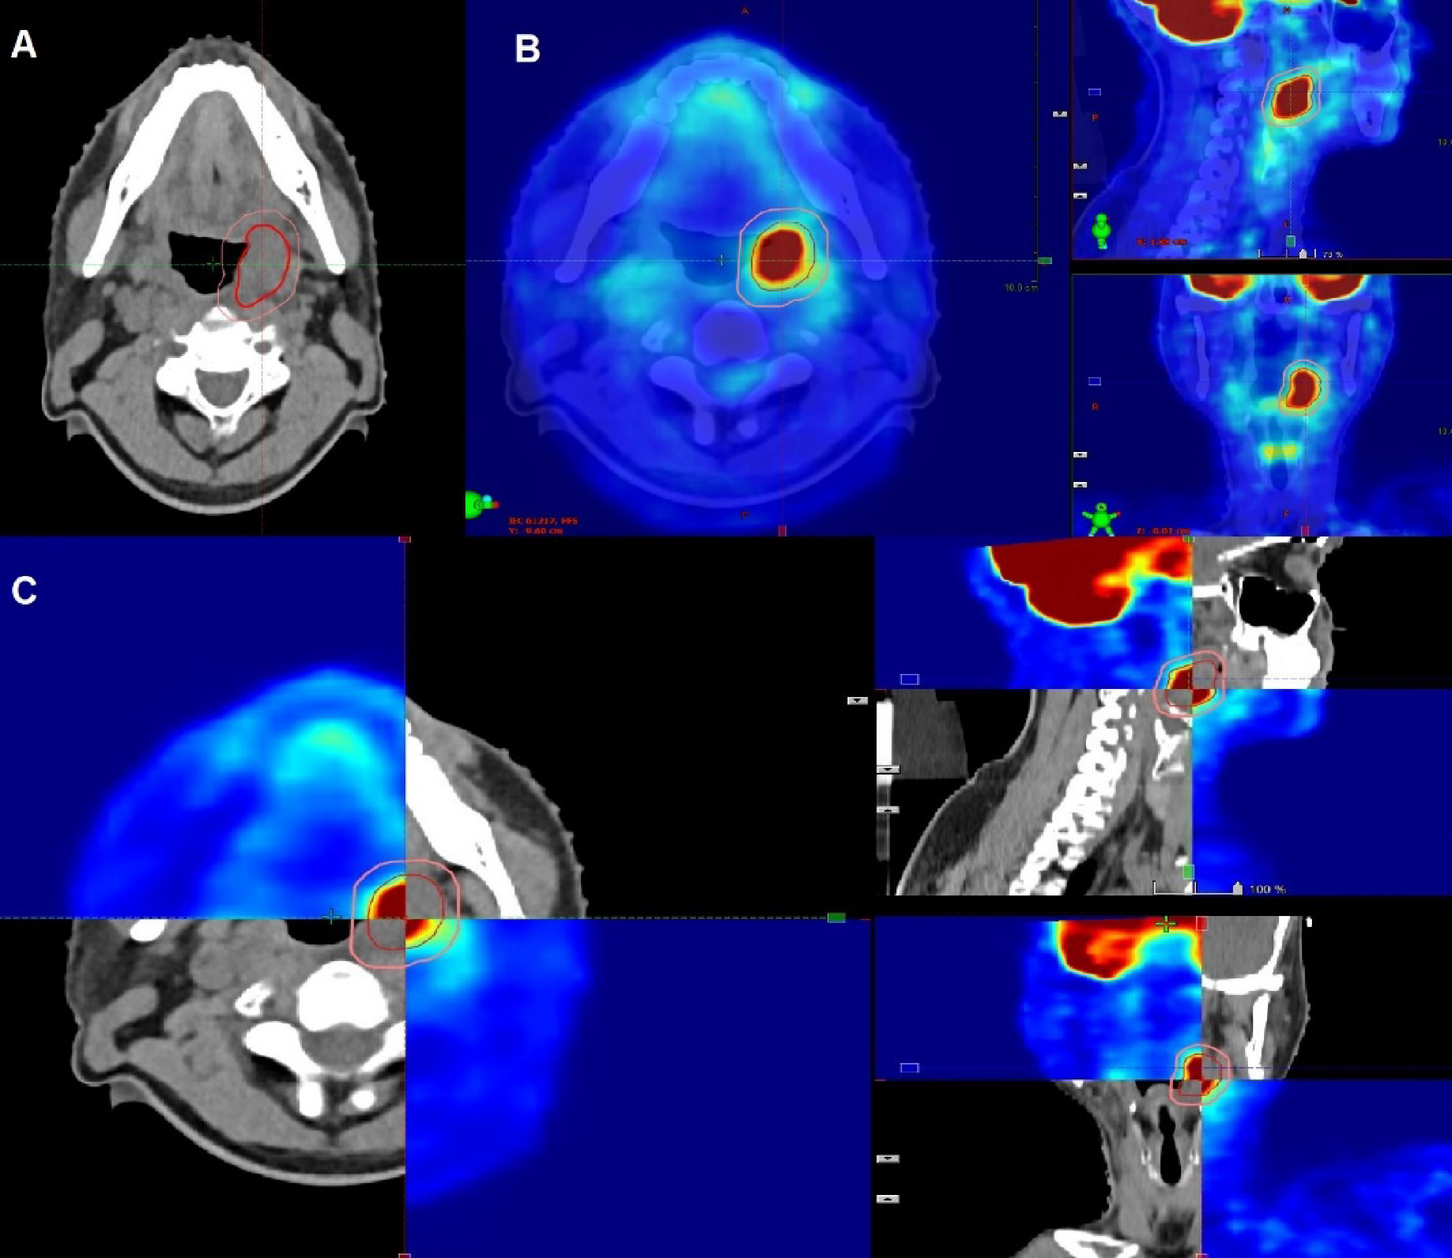

Fig. 1

GTV & PTV contouring on CTsim scan (A), PET CT scan (B) and fused scan (C) in a patient receiving definitive reirradiation.